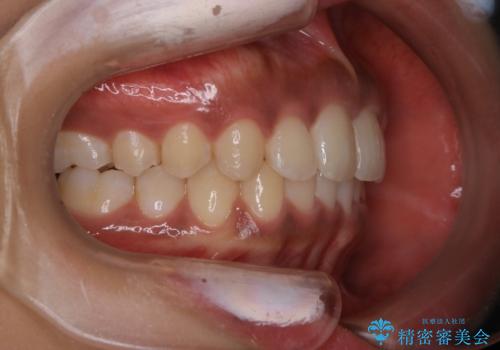

インビザライン矯正 歯を抜かずに出っ歯を改善!

- 出っ歯と前歯の隙間が空いていることを気にされて来院されました。

また、自然な感じで口元を下げていとのことでした。

奥歯のかみ合わせが問題なかったため、上顎の前歯の隙間を閉じるとともに、上顎の歯の側面を削ることをメインにして、出っ歯を改善する治療計画としました。

上顎の歯の傾きを変えるうえで、下顎の歯とのバランスのことも考え、下顎の歯の側面も削ることを加えています。

また、今回は口元を変えたい中に、劇的な変化は避けたいとのことだったので、抜歯をしない計画としています。

抜歯をしない場合、口元の変化は感じにくいですが、前歯の傾きが変わることで、口の閉じやすさは感じていただけたとのことです。

症例にもよりますが、本症例は奥歯のかみ合わせに問題がなかったので歯の側面を削ることメインに、前歯の傾きを改善することができました。

抜歯を行う場合や抜歯をしなくても奥歯の位置をずらす場合は、治療期間が長期化することが多いですが、今回は歯を削ることで改善できたため、短期間で治療を完了することができました。